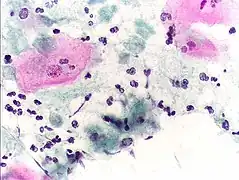

High-grade squamous intraepithelial lesion

Squamous metaplasia of the cervix, with typical features. Pap stain.

Pap tests commonly examine epithelial abnormalities, such as metaplasia, dysplasia, or borderline changes, all of which may be indicative of CIN. Nuclei will stain dark blue, squamous cells will stain green and keratinised cells will stain pink/ orange. Koilocytes may be observed where there is some dyskaryosis (of epithelium). The nucleus in koilocytes is typically irregular, indicating possible cause for concern; requiring further confirmatory screens and tests.